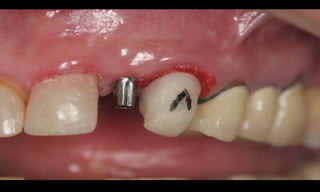

Resultados estéticos periimplantares otimizados

(Abboud, M. IJOMI, 2005).